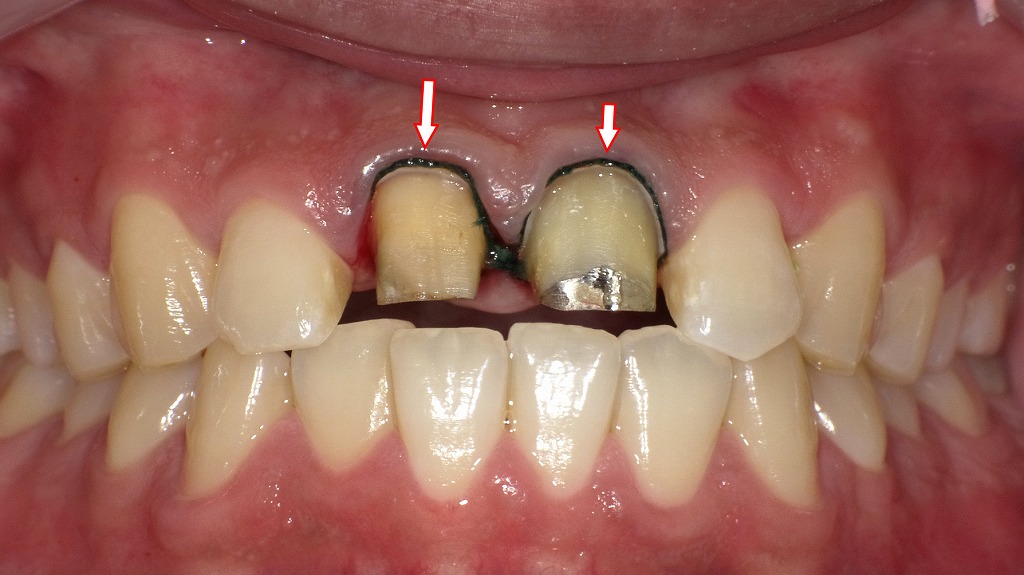

圧排糸を歯肉溝内に挿入

この画像は、上顎中切歯(右上1番・左上1番)の補綴処置(被せ物作製)のために印象採得(型取り)を行う直前の状態を示しています。

赤い矢印で示されている部分には、**圧排糸(あっぱいし)**と呼ばれる細い糸が歯肉溝内に挿入されています。

🔍 解説

🦷 圧排糸とは

圧排糸は、歯と歯ぐき(歯肉)の境目に一時的に挿入する糸で、

歯肉をやさしく押し下げて歯の縁(マージン)を露出させるために使用します。

この処置によって、

- 歯と歯ぐきの境目まで精密に型を取ることができる

- 技工物(クラウン・ブリッジなど)の適合性を高める

- 仕上がりの審美性や清掃性を向上させる

といった効果があります。

📸 画像の状況

- **中央の2本の歯(上顎中切歯)**は、すでに支台歯形成(削って形を整える処置)が完了しています。

- 歯の周囲(歯頚部)に圧排糸が入れられており、歯肉がわずかに開いてマージン部が見えています。

- 支台歯表面は黄色っぽく見えますが、これは象牙質またはメタルコア(土台)の露出によるものです。

- このあと**精密印象(シリコン印象材など)**を流して、被せ物(セラミッククラウンなど)の製作工程に進みます。